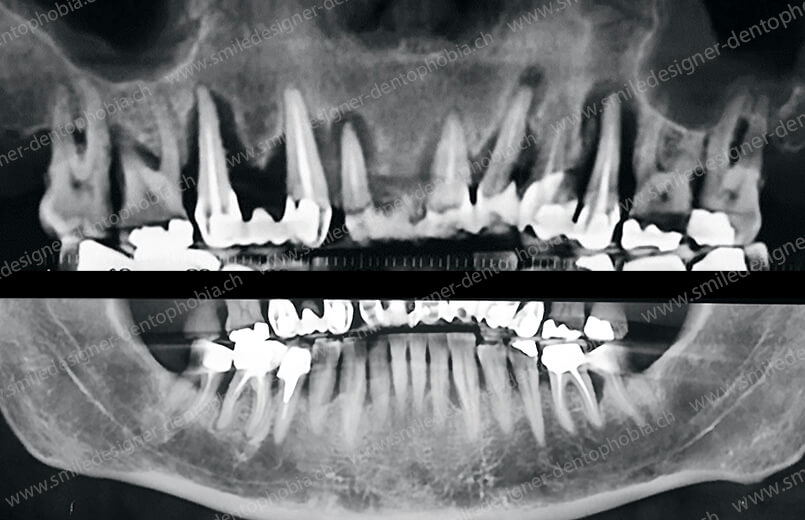

Cas clinique « GOLD STANDARD MCI » bi-maxillaire : Bridge implanto-porté sans extension postérieure (ALL ON 10). Version définitive des bridges avec un cosmétique en céramique.

Cas clinique « GOLD STANDARD MCI » bi-maxillaire : Bridge implanto-porté sans extension (ALL ON 8) au maxillaire et à la mandibule. Version définitive des bridges avec un cosmétique en céramique.

Cas clinique « GOLD STANDARD MCI » maxillaire : Bridge implanto-porté sans extension (ALL ON 8). Version définitive des bridges avec un cosmétique en céramique.

Cas clinique « GOLD STANDARD MCI » maxillaire : Bridge implanto-porté sans extension (ALL ON 10). Version définitive des bridges avec un cosmétique en céramique.